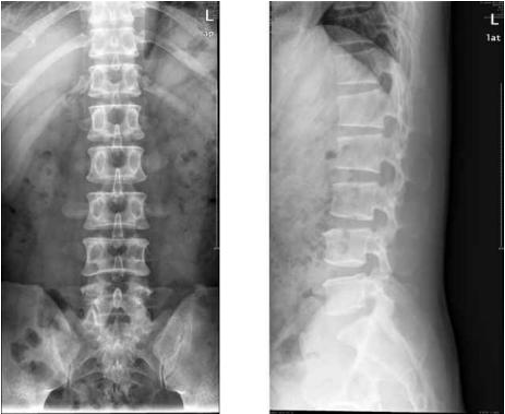

“第一板斧”,首當其衝是我們的腰椎X線檢查(如圖1)。它的主要作用有下面這些:檢查是否有骨質異常;顯示是否有脊柱側彎;評估椎間隙是否有狹窄。

當然,它也有其自身不足之處,這個檢查有微量輻射;一些前後重疊的組織結構顯示不清;它對於椎間盤以及軟組織結構的觀察效果有限(如腰背部肌肉、皮下脂肪、筋膜)。